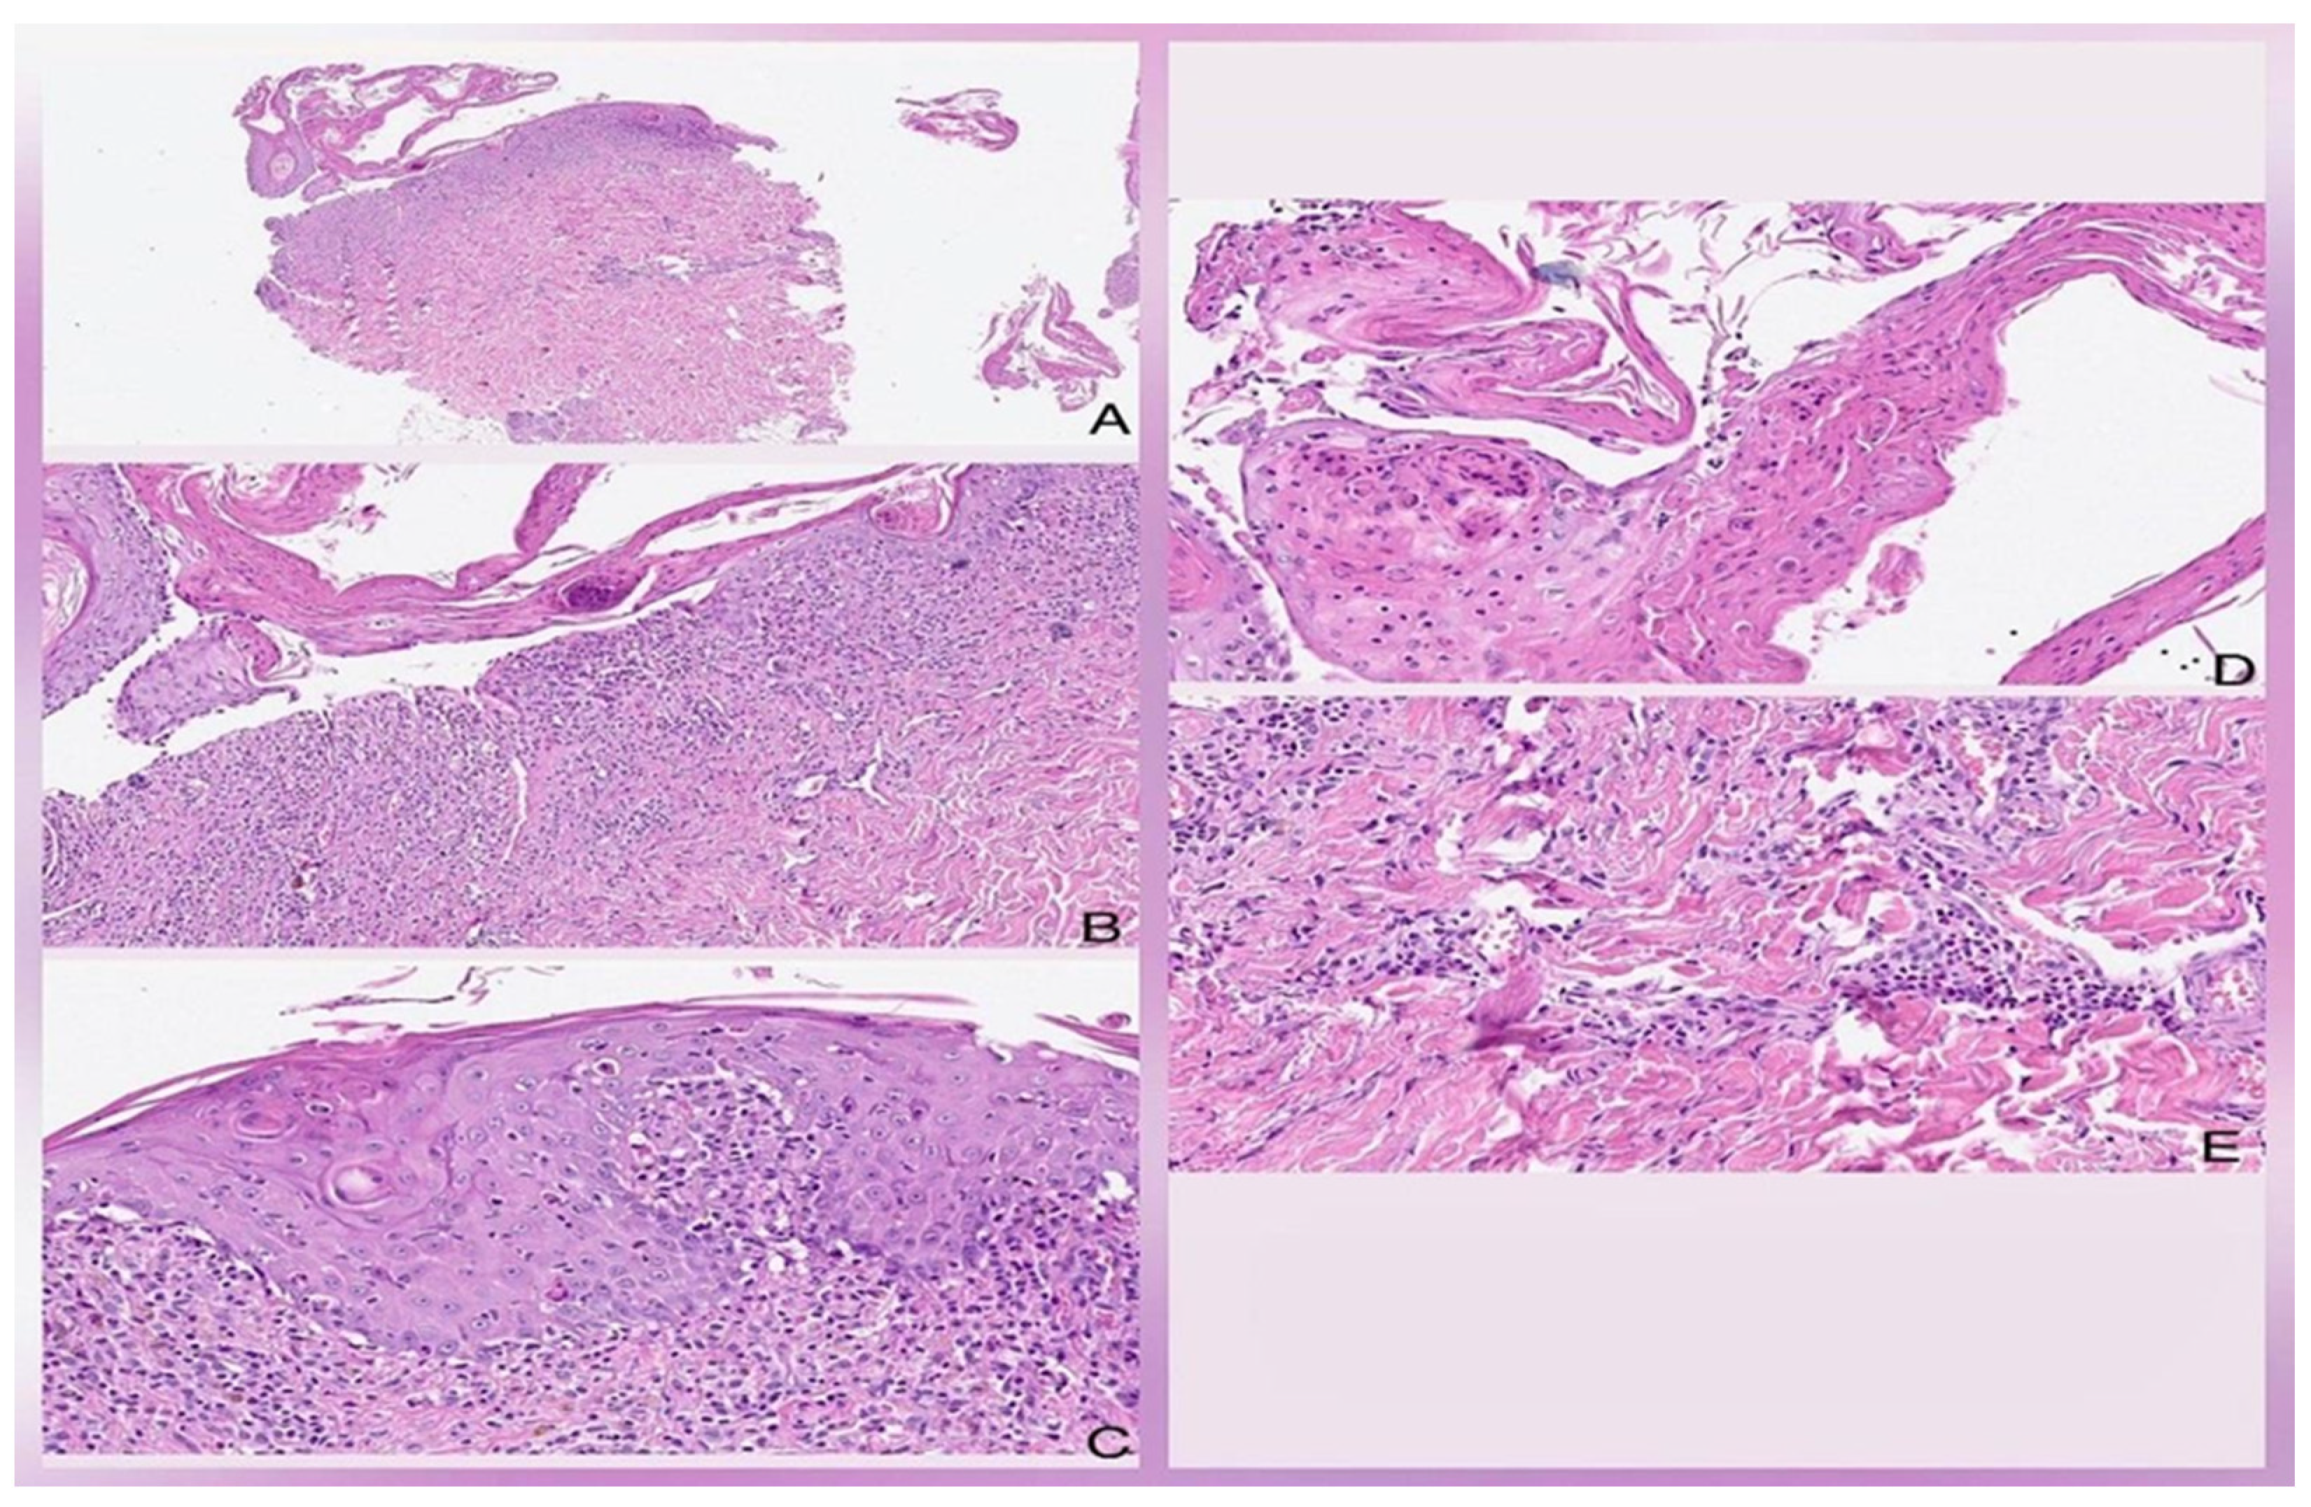

Figure 2.

Histologic findings are characterized by the presence of spongiotic and acantholytic lesions, with numerous full-thickness apoptotic and necrotic keratinocytes of the epidermis in some areas (A). Dense inflammatory infiltrate of the mixed interface, predominantly lymphocytic and polymorphonuclear (B). Disruption of the epidermis with numerous apoptotic bodies, incontinence of pigment, and extravasation of erythrocytes (C). Acantholysis and full-thickness necrosis of the epidermis (D). Vasculitis at the level of deep vessels is associated with a dense lymphocytic and neutrophilic infiltrate (E). Hematoxylin and eosin. Original magnification 2× (A), 10× (B), 20× (C–E).

A 50-year-old man arrived at the emergency department with a widespread scaly rash covering his face, chest, abdomen, and back. He also had facial swelling, lymphadenopathy, and mucous membrane involvement (see Figure 1A,B). Upon admission, his physical examination revealed a temperature of 37.8 °C, weight of 80 kg, height of 1.78 m, and a BMI of 25.3. According to family members, he had been taking 300 mg of allopurinol for two weeks before the rash’s appearance as he was diagnosed with hyperuricemia. He had also experienced a fever and upper respiratory tract illness the week before. The patient had a history of type 2 diabetes mellitus for 15 years, multiple lower limb amputations due to diabetic neuropathy and poorly controlled hypertension being treated with losartan and metformin and rapid-acting insulin. Upon admission, we stopped the suspected drug using the Naranjo score. The patient was uncooperative and obtunded. Laboratory abnormalities included a Hb of 8.97 g/dL, hematocrit (HTO) of 29.3%, white blood cells (WBC) of 19.3 K/µL, eosinophils of 0.002 K/µL, platelets of 295,000/mm3 plasma glucose level of 143 mg/dL, serum creatinine level of 10.3 mg/dL, BUN level of 150 mg/dL, serum potassium level of 7.2 mmol/L, serum sodium level of 156 mmol/L, and abnormal liver function tests including AST level of 120 UI/L, ALT level of 113 UI/L, ALP level of 439 UI/L, total bilirubin level of 3.3 mg/dL, direct bilirubin level of 1.9 mg/dL, and LDH level of 331 UI/L. We consulted nephrology for hemodialysis and dermatology for a suspected drug-induced skin reaction. Dermatology performed a skin biopsy, which revealed a spongiotic and acantholytic lesion, suggesting an epidermal necrolysis (see Figure 2A–E). Although no tests were carried out to identify the reactivation of HHV 6–7 or EBV, the human pathology department diagnosed Stevens–Johnson syndrome, and the clinical features met the criteria for DRESS. We initiated intravenous corticosteroid therapy at a dose of 4 mg/kg/BID, which was later increased to 8 mg/kg/BID due to poor clinical response (see Figure 1B).